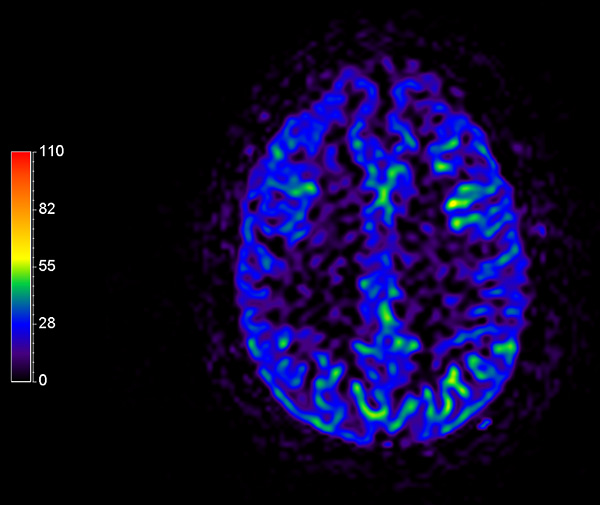

Comprehensive Brain imaging at 3.0T

• Clinical Application